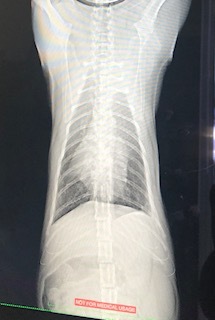

・レントゲン検査

肺も白い部分は変化ありませんでした。